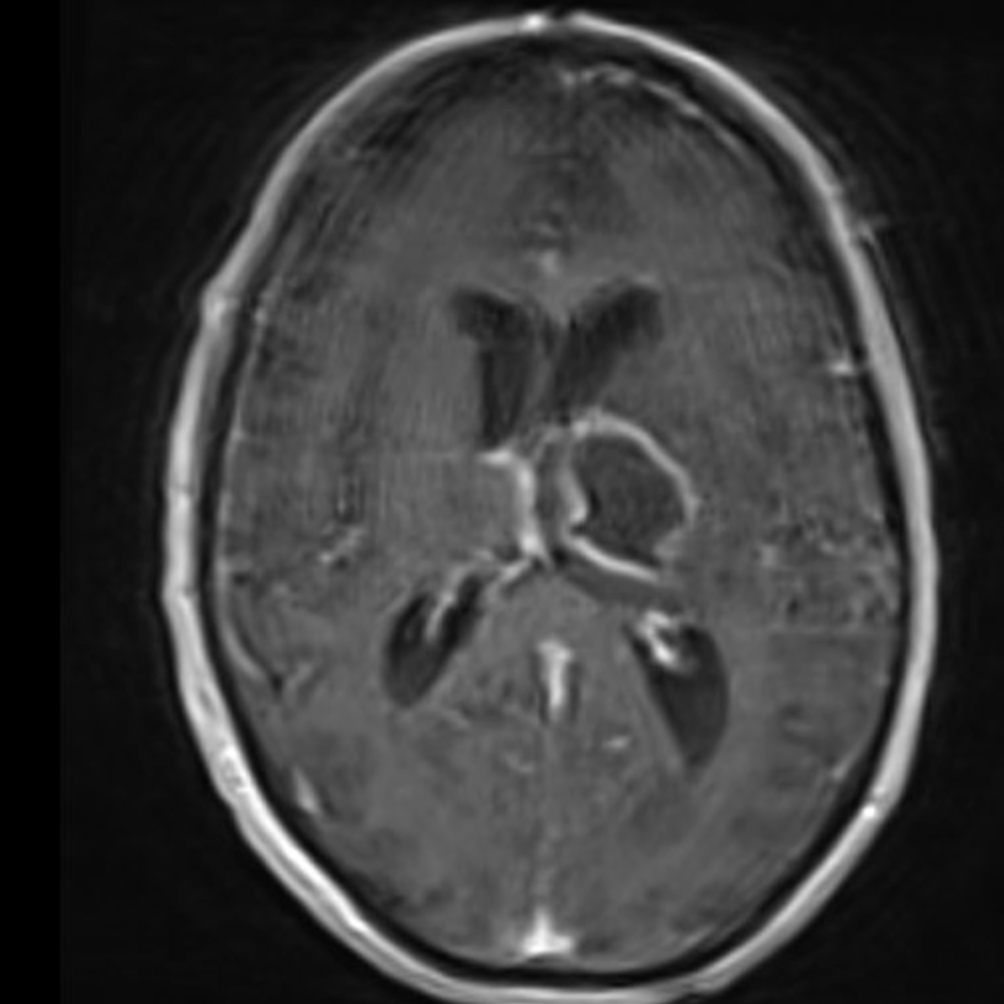

Kontrastmittel aufnehmende Raumforderung (sog. Balkengliom) in einem axial geschichteten T1-KM MRT des Neurokraniums (cMRT).

Die das Verhalten einer Raumforderung im Schädelkinneren im KM-MRT (Kontrastmittel-MRT) kann oft schon entscheidende Informationen liefern über die wahrscheinliche Art des Tumors. Das ersetzt nach aktuellem Wissensstand jedoch keine feingewebliche Untersuchung!